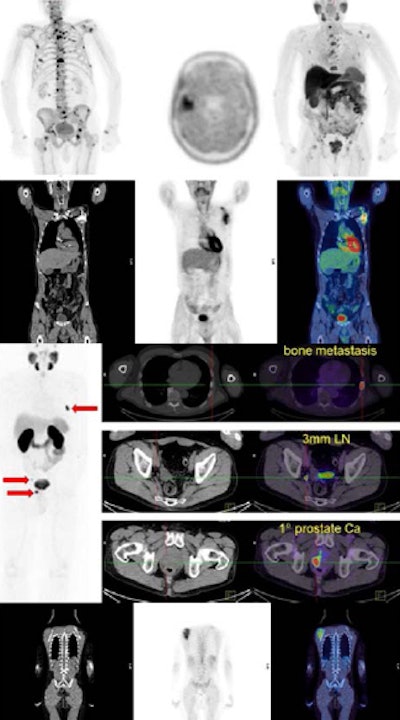

PET/CT images show a Hodgkin's lymphoma patient with a negative PET scan after chemotherapy. There is high uptake in lymph nodes on both sides of the neck prior to treatment (above), which resolved after chemotherapy (below). Physiological uptake is also seen in the heart and bladder. Images courtesy of Dr. Sally Barrington, reader in nuclear medicine, PET Imaging Centre at St Thomas' Hospital in London.

PET/CT images show a Hodgkin's lymphoma patient with a negative PET scan after chemotherapy. There is high uptake in lymph nodes on both sides of the neck prior to treatment (above), which resolved after chemotherapy (below). Physiological uptake is also seen in the heart and bladder. Images courtesy of Dr. Sally Barrington, reader in nuclear medicine, PET Imaging Centre at St Thomas' Hospital in London.Other short-lived tracers like N-13 ammonia and carbon-11 labeled compounds are produced in a cyclotron that needs to be on the same site as the scanner. Fluorinated tracers and generator-produced tracers may become more widely available, they pointed out.